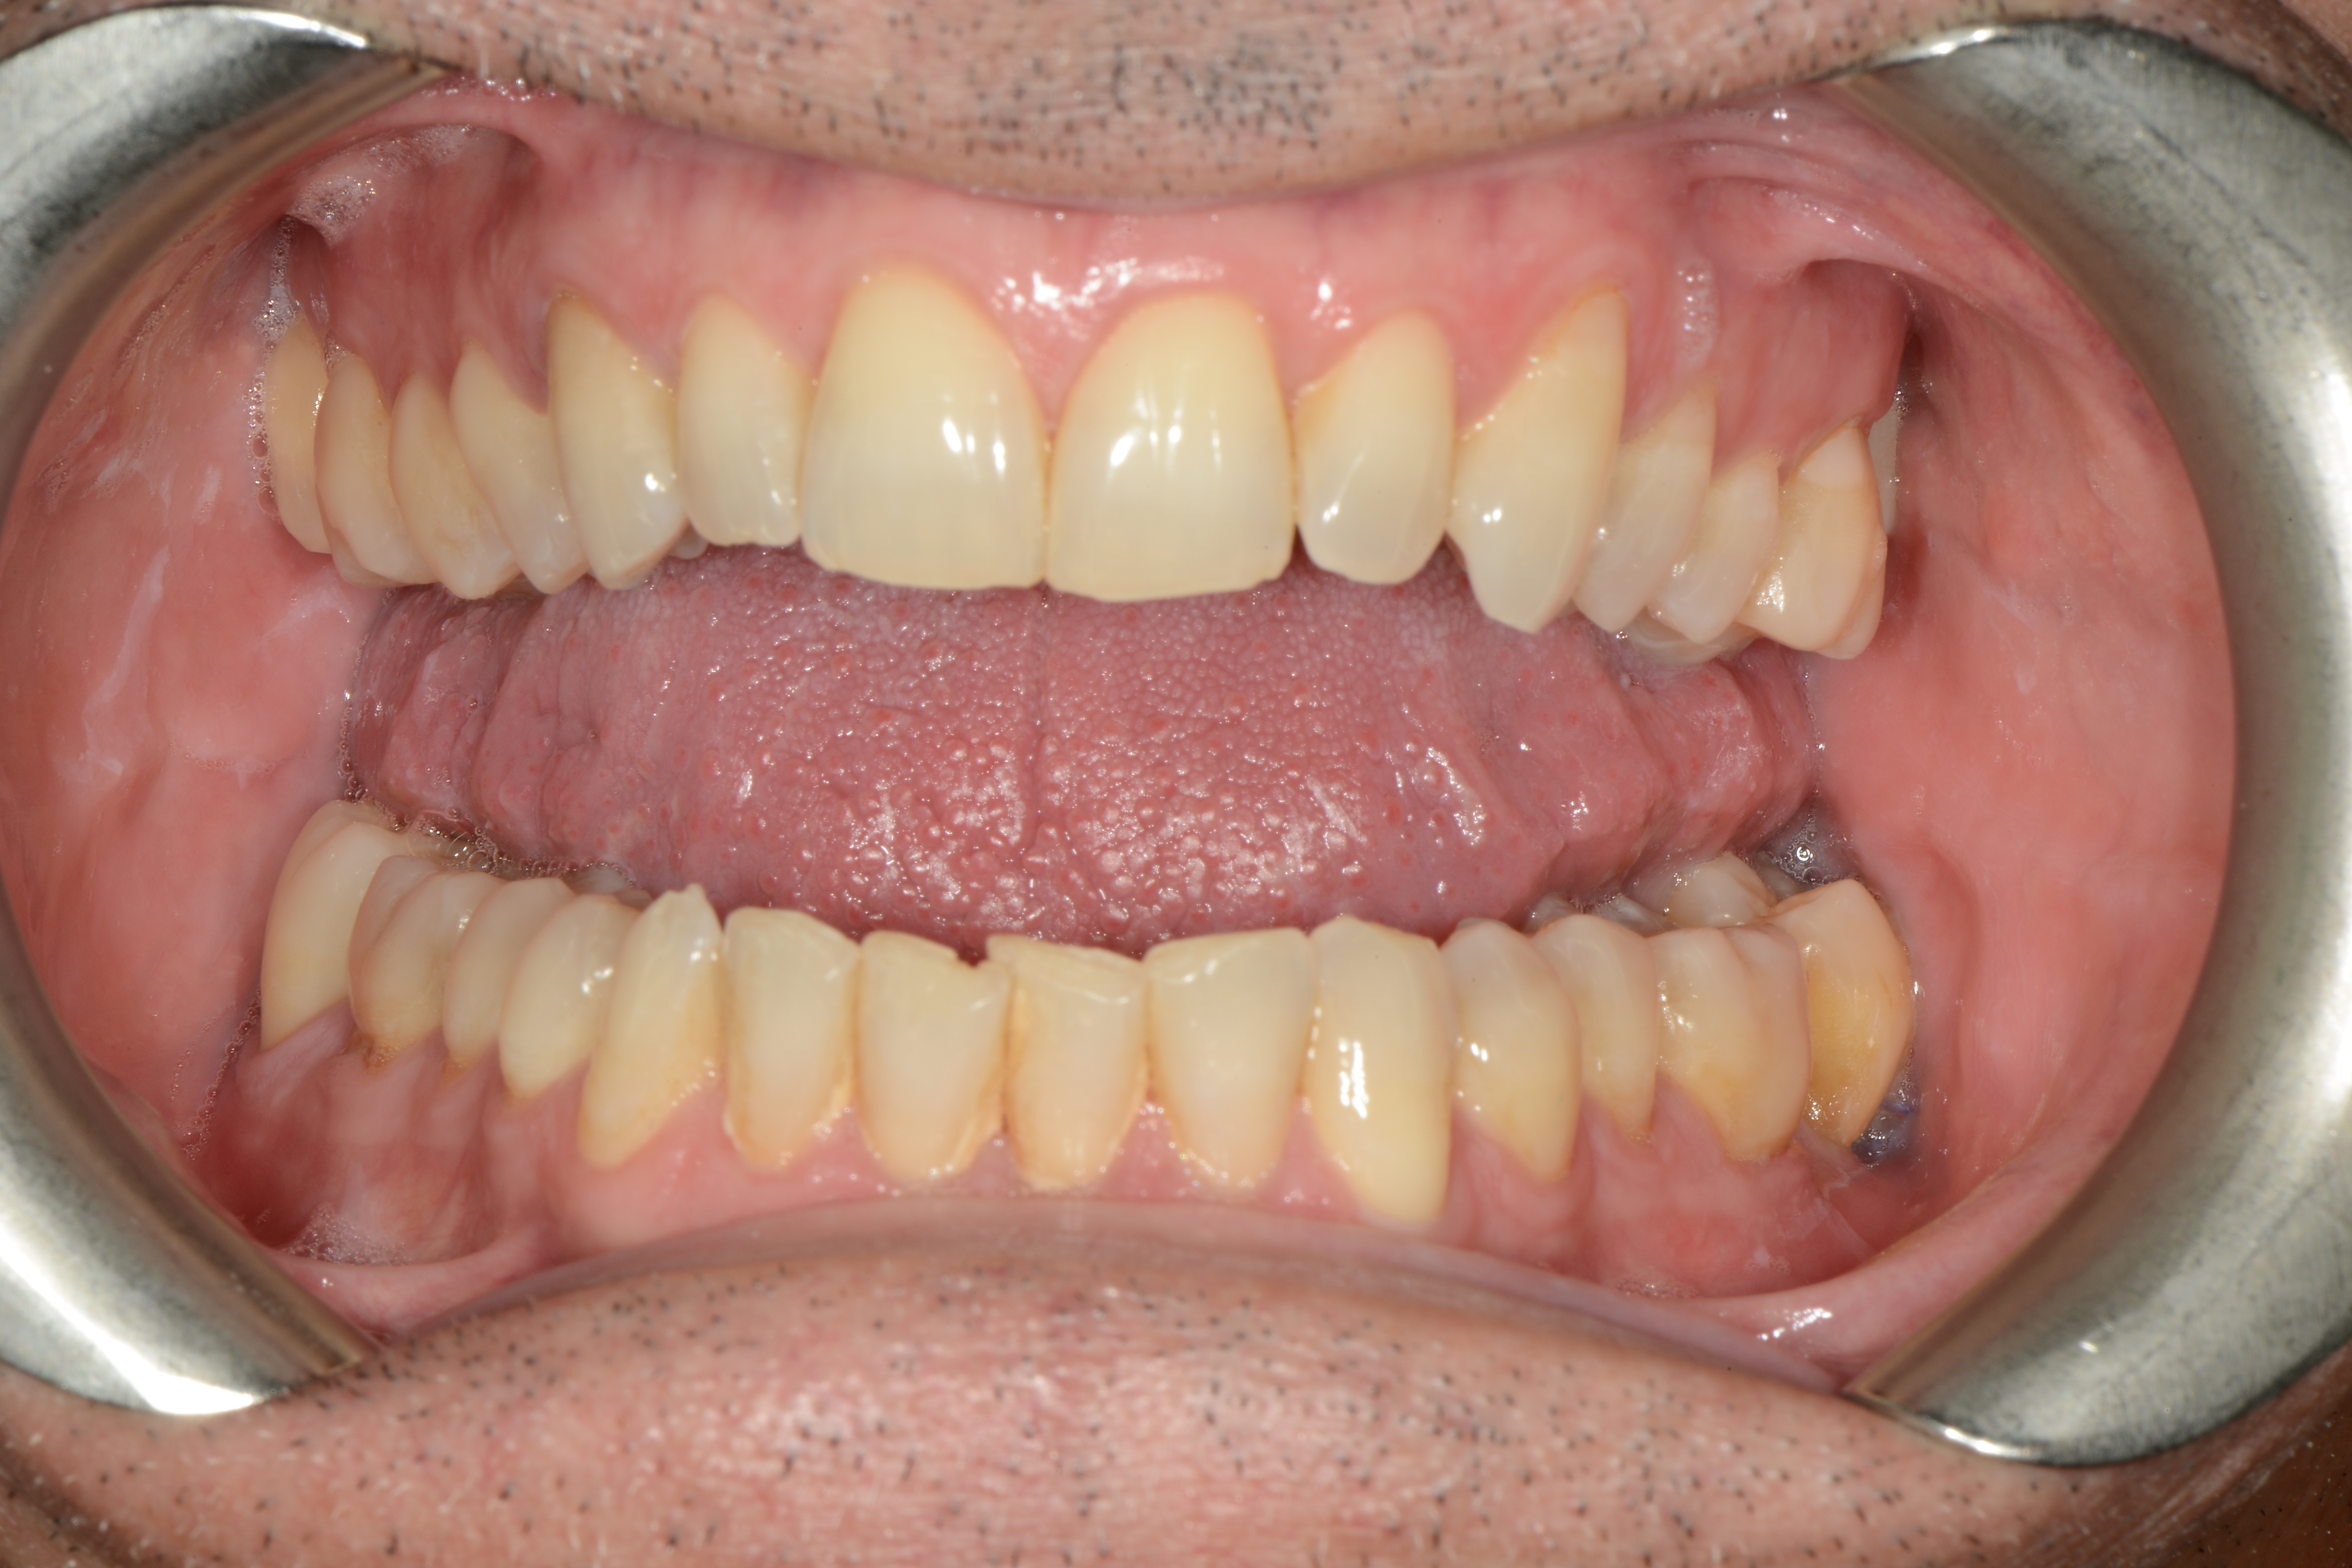

After the first phase of aligner treatment, we had achieved better inter-arch coherence, better maxillary arch expansion, and some space for improving the anterior tooth proportions restoratively (Fig. 19). We then temporarily restored the anterior teeth directly with composite, closing the spaces, improving the tooth proportions and further increasing the maxillary arch expansion (Fig. 20). We used restorative arch expansion to reduce the orthodontic destabilisation of the teeth to achieve the correct inter-arch coherence and retain the teeth in the cortical bone.38 A refinement aligner phase was undertaken to improve the final alignment of the gingival zenith and to improve the inter-arch coherence (Fig. 21). The periods of the first orthodontic phase and of the refinement were used to augment the mandibular and maxillary bone and to place the implants (Fig. 22). At the end of the orthodontic treatment, the case was finalised with ceramic veneers in the anterior area and temporary restorations on the implants in the posterior area (Figs. 23–26).

The provisional phase of about four months was important to allow the peri-implant tissue to mature and to teach the patient to chew correctly with chewing gum, cotton rolls and silicone masticatory sticks. This is fundamental training for the patient to achieve the correct alternating unilateral masticatory cycle needed to obtain the ideal rehabilitation of the masticatory system. We wanted the patient to achieve ideal masticatory and swallowing function. After sufficient rehabilitation time, we finalised the case with posterior zirconia crowns screwed on to the implants (Fig. 27).26